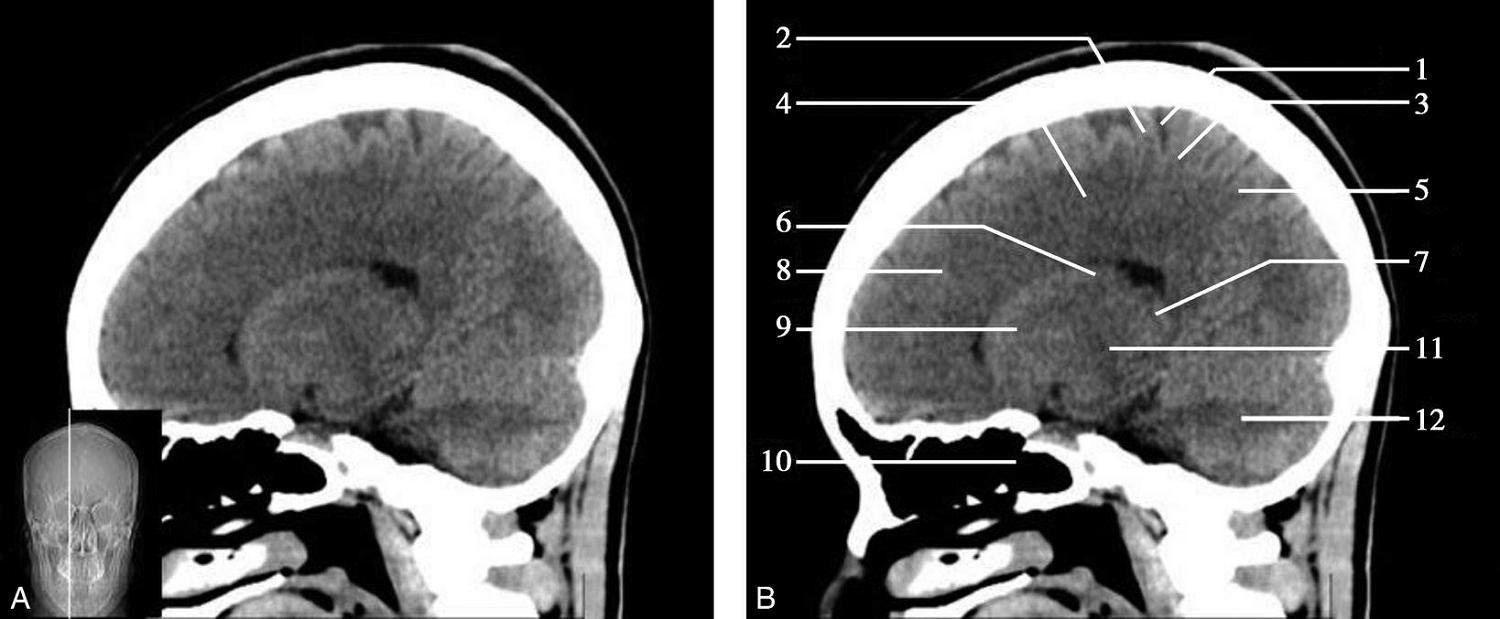

重要结构:胼胝体、垂体、中脑导水管、扣带回、中央沟、第三脑室、斜坡(图1-2-59、图1-2-60)。

图1-2-59 正中矢状面CT

A.矢状面;B.矢状面标注

1.中央沟;2.扣带回;3.胼胝体体部;4.侧脑室;5.中脑;6.胼胝体膝部;7.穹隆;8.第三脑室;9.胼胝体压部;10.垂体;11.中脑导水管;12.第四脑室;13.脑桥;14.蝶窦;15.斜坡;16.小脑扁桃体;17.延髓

此层面可显示胼胝体全貌,它位于层面中央区域,是呈上凸下凹的弧形结构,由前向后分为嘴、膝、体和压四部分。扣带回环绕胼胝体上方,扣带沟位于扣带回的上方。大脑半球中部和后部分别可见较深且恒定的中央沟和顶枕沟。中央沟为是额叶顶叶分界标志。

胼胝体下方为侧脑室及穹窿,第三脑室借穹窿与前上方的侧脑室体部分开,背侧丘脑的内侧面以及中脑顶盖分别为第三脑室的外侧壁和底。第三脑室向前籍室间孔与侧脑室相通,向下经中脑导水管通第四脑室。中脑腔狭窄呈管状,即称为中脑导水管,中脑导水管畸形,常见者为导水管的分叉畸形和狭窄,其次可见中脑导水管膈膜,造成先天性脑积水。

脑干由中脑、脑桥和延髓组成,自第三脑室底向下后稍斜行,移行于颈髓。由上至下,脑干腹侧可见脚间池、桥前池和延髓池,脑干背侧可见大脑大静脉池、四叠体池和小脑延髓池。

垂体位于蝶鞍内,其前部为腺垂体,后上部分为神经垂体。垂体下方为鞍底及蝶窦,上缘因鞍膈存在而平直,垂体借垂体柄向上连于丘脑下部。垂体的前上方见视交叉和视束。斜坡作为前颅窝底的重要组成部分与多个重要结构相比邻,矢状位呈三角形,颅内肿瘤或颅外鼻咽部恶性肿瘤均可侵犯至此,原发肿瘤常见为脊索瘤。小脑幕居枕叶和小脑之间,向后下连接窦汇,向前至中脑后方游离,称小脑幕切迹。小脑幕下方为小脑扁桃体。成年人小脑扁桃体下缘由枕骨大孔向下疝入椎管超过5mm称为Chiari畸形,以矢状位显示最佳。